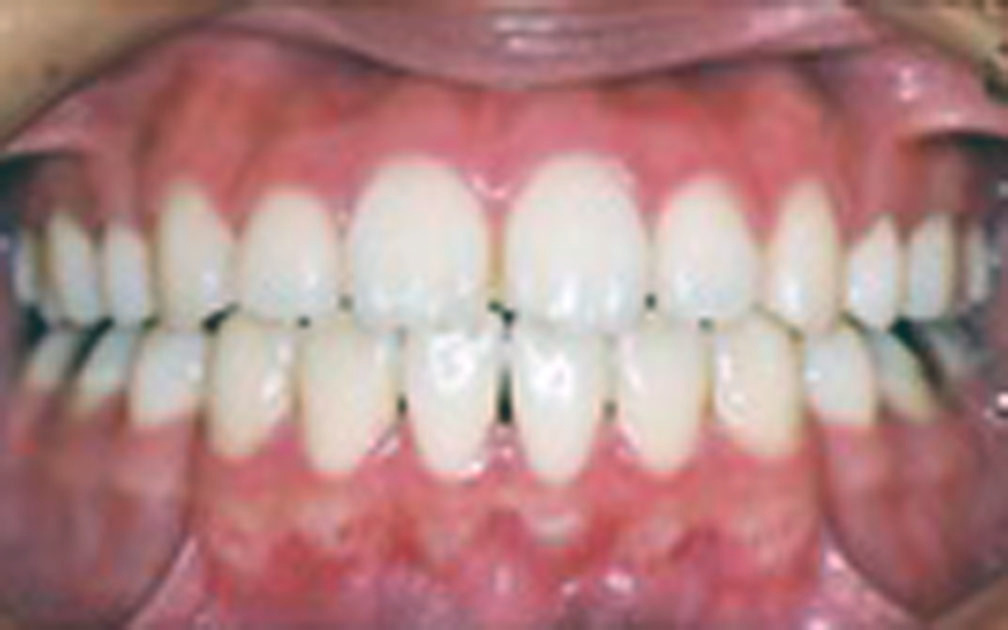

矯正の症例3 (診断名)叢生(ソウセイ)

(患者様の主訴)八重歯が気になる

(治療開始年齢)23歳4カ月

(主な治療装置)エッジワイズアプライアンス

(抜歯部位)上下第1小臼歯4本抜歯

(治療期間)1年10カ月

(治療費)¥805000

(個別リスク・副作用)叢生が著しいため動的治療後長期にわたる保定が必要となる。

歯牙の移動量が大きいため歯根が短根になるリスクがある。

叢生が改善されるまで、ブラッシングがしにくい状態が続くために齲蝕になるリスクがある